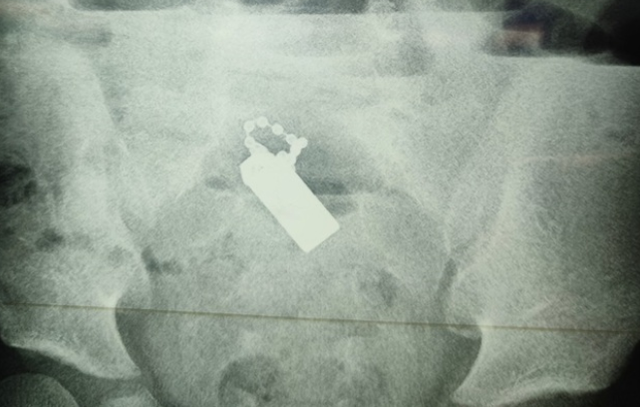

| Hình ảnh kiểm tra cho thấy dị vật cản quang nằm trong đường tiêu hóa của bệnh nhi. |

Ths BS Lê Thọ Đức, phẫu thuật viên chính của ca mổ, cho biết dị vật là chuỗi hạt kim loại nhỏ kèm đai ốc và một miếng nam châm hình chữ nhật dài 2cm. Miếng nam châm hút các mảnh kim loại gây tắc nghẽn ruột và hoại tử, thủng 3 vị trí ở ruột, phân vào ổ bụng gây nhiễm trùng nặng.

Dị vật là chuỗi hạt kim loại nhỏ kèm đai ốc và một miếng nam châm hình chữ nhật dài 2cm.